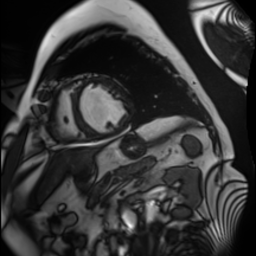

ACDC dataset [2] is a four-class segmentation benchmark (background, right ventricle, left ventricle, myocardium) comprising 100 patient scans. Following the setup in BCP and related works, we allocate 70 scans for training (1,312 images), 10 for validation, and 20 for testing. For semi-supervised scenarios, we explore 5% and 10% splits of the training data, equivalent to 68 and 136 images respectively, to align with prior semi-supervised methodologies and simulate low-data conditions.

Synthetic Data: For our experiments, high-fidelity synthetic images are generated using StyleGAN2-ADA [16] as described in Section 3.1.2. The model is trained exclusively on the limited percentage of real labeled data available for each dataset (e.g., 5% or 10%). For instance, when using 10% labeled data (136 images for ACDC or 56 for FIVES), StyleGAN2-ADA is trained solely on these specific images. Figure 3 shows random synthetic samples generated for both ACDC and FIVES datasets at 5% and 10% labeled data splits.

5.1 Results on ACDC Dataset

Quantitative Results: Table 1 presents segmentation results on ACDC dataset [2] across 5% and 10% labeled data conditions. As the results demonstrate, SRA-Seg achieves superior performance compared to all the other models in the 10% labeled data (with 90% synthetic unlabeled data) scenario, coming a close second in the 5% scenario as well. SRA-Seg also obtains better results than the real unlabeled data scenario, demonstrating the potential to significantly reduce the reliance on extensive real data collection.

Qualitative Results: Figure 6 presents a visual comparison of segmentation results obtained for the 10% data split on the ACDC dataset. As shown in the overlay highlights, SRA-Seg results in the least errors and achieves significant improvements compared to the other approaches.